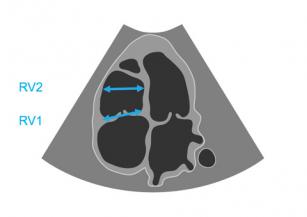

Evaluating right ventricular size and function with the help of echo 21st Jun 2017 - Helen Rimington, PhD After watching this video, you will recognize right ventricular dilatation, significant hypertrophy and hyper- and ...